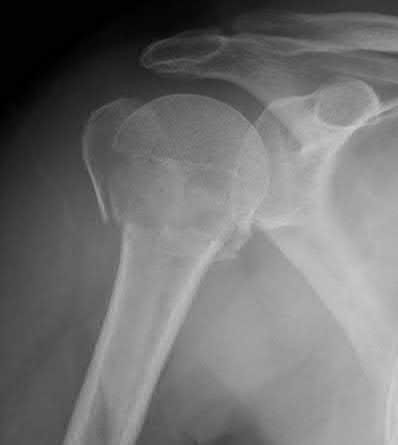

A 55-year-old patient presents with a slowly enlarging, painful mass in the proximal humerus.

Biopsy reveals a hyaline cartilage matrix with cellular atypia, confirming a diagnosis of central conventional chondrosarcoma. Which of the following genetic mutations is most frequently identified in this specific tumor?